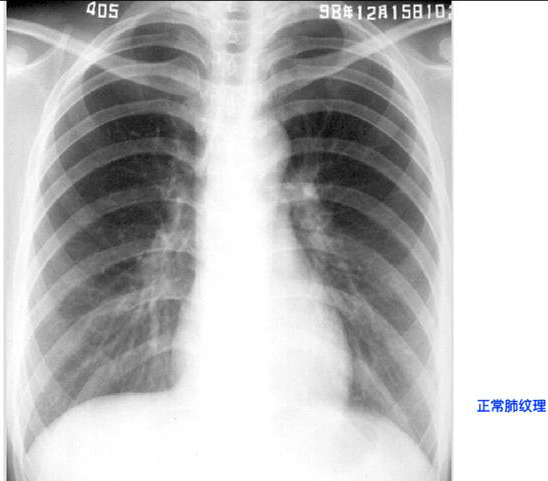

照片名称:正常肺纹理